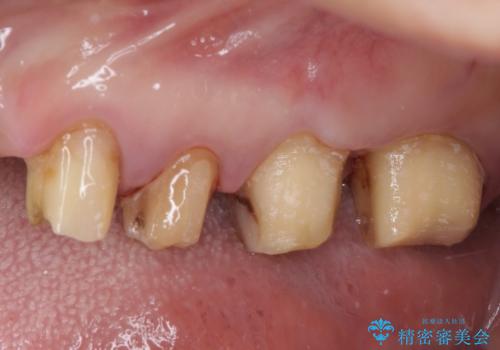

- 歯を磨く度に奥歯から出血するとのことで来院された患者様です。

歯周ポケット検査を行ったところ、6-8mmの歯周ポケットが散見され(正常では3mm以下)、歯周病治療が必要と判断されました。

仮歯に置き替え、歯周外科処置(APF、歯肉弁根尖側移動術)による歯周ポケット除去を行った後に、オールセラミッククラウンにて補綴することとしました。